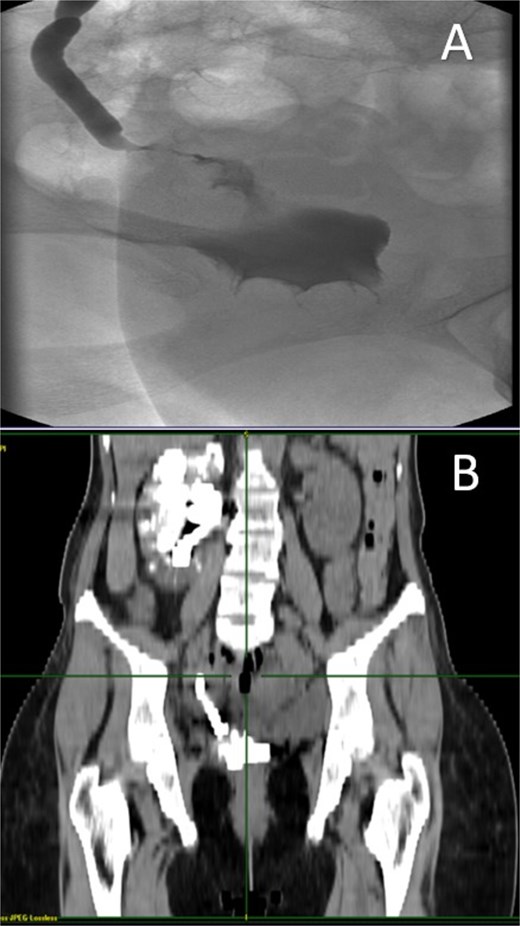

A CT nephrotomography with contrast enhancement was performed and identified an abnormal communication between the right ureter and the vagina reporting an UVF (Fig. 1). Moreover, a retrograde cystography was also performed without any findings. Due to the high suspicion of an intraoperative ureteral trauma, a conservative management was decided and a percutaneous nephrostomy was placed in the right kidney, aiming to prevent further urinary leakage from the vagina and to avoid further dilation of the kidney.

A: Diagnostic nephrotomography showing the existence of an UVF. B: CT nephrotomography showing the abnormal passage of intravenous contrast enhancement fluid from the ureter to vagina, confirming the existence of an UVF.